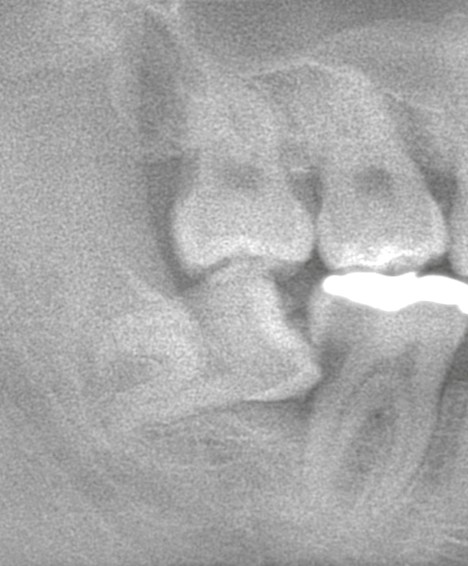

* 半分だけ顔を出している

* 横向きに傾いて隣の歯を押している

* 垂直に挺出して咬み合わせに干渉している

こうした状態を放置すると、歯列全体に圧力がかかり、歯並びの乱れや早期接触による咬合のズレを引き起こします。その結果、顎関節に負担がかかり、顎関節症(顎の痛み・開口障害・関節音など)を悪化させる要因にもなります。